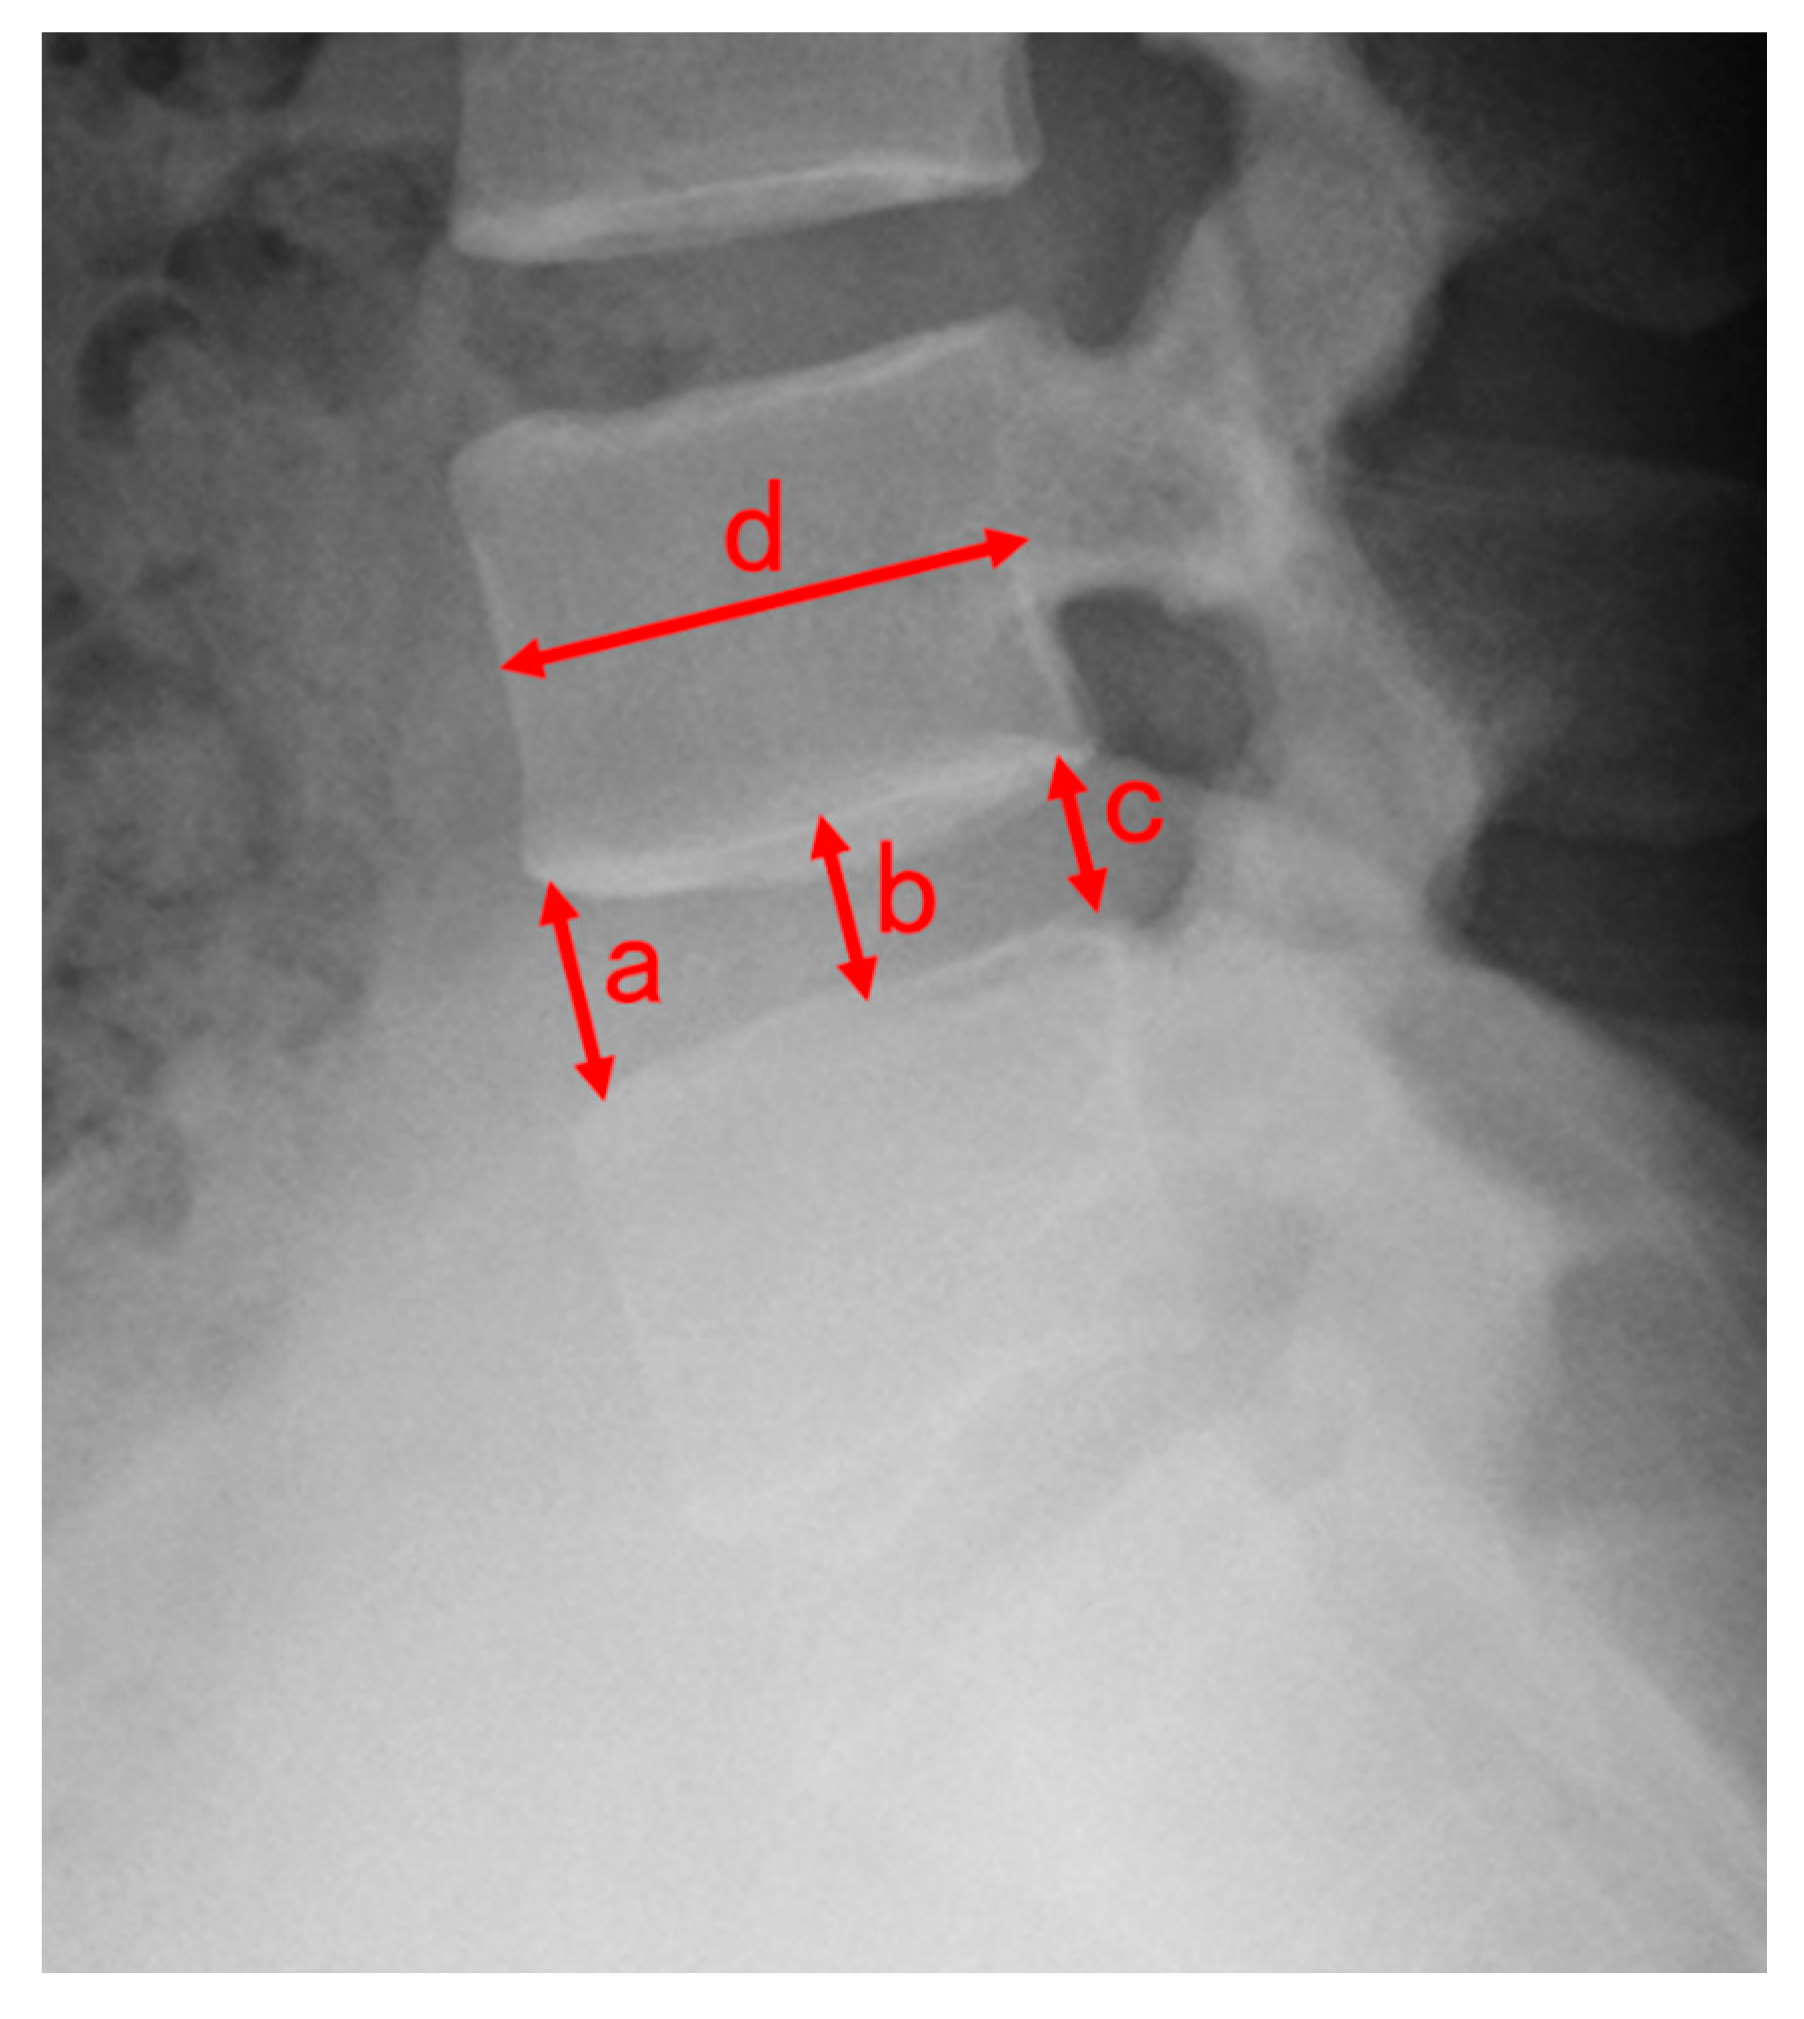

2.6. Evaluation of Disc Height

- Inoue, H.; Ohmori, K.; Miyasaka, K.; Hosoe, H. Radiographic evaluation of the lumbosacral disc height. Skelet. Radiol. 1999, 28, 638–643. [Google Scholar] [CrossRef]

| Preoperative DHI, median (IQR Q25–75) | 0.23 (0.19–0.29) | 0.24 (0.22–0.27) | 0.43 |

| Postoperative DHI, median (IQR Q25–75) | 0.22 (0.18–0.27) | 0.22 (0.20–0.24) | 0.69 |

| DHI ratio, median (IQR Q25–75) | 0.94 (0.89–1.03) | 0.90 (0.79–0.95) | <0.05 |